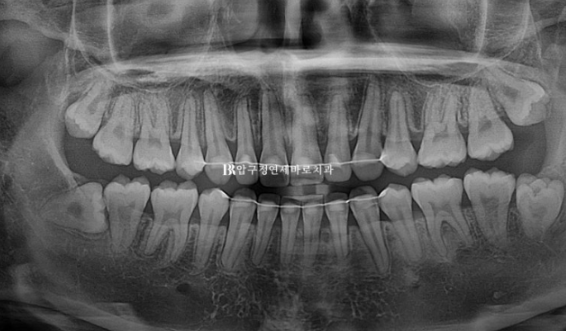

치근평행도 양호하고 별다른 부작용이 보이지 않습니다.